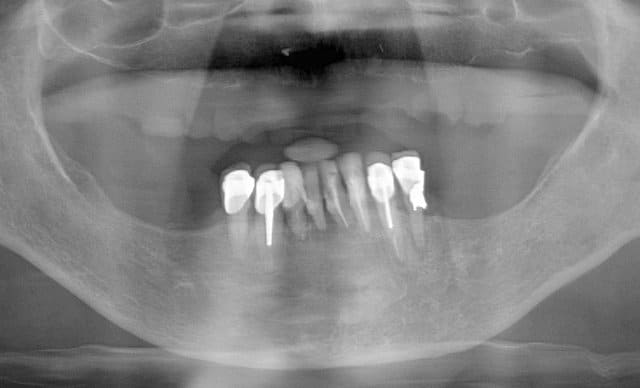

Pour la distance inter-implants c est une bonne remarque, le distance réglementaire est de 2/3mm en méthode conventionelle , ici c´est une variante du flapless en forant de manière à condenser l´os via un foret à 3 faces. En préservant le périoste on a remarqué que cette distance réglementaire pouvait être plus petite. C est une observation , qui marche (en flaples) dans ma pratique et dans celles de mes confrères Allemands, à ma connaissance pas enormément documenté . Ceci dit il y a un livre en francais qui en parle "implantologie flapless" de Byung Ho Choi et wilfried Engelke (Pr de Göttingen).

Sur le cas posté au début la dernière radio est après deux ans post OP. Ci dessous un autre exemple.

Les 12 premières photos sont un même cas avec implantation immédiate.

Le deuxième cas c est les photos 13 14 15 , (la photo 14 et 15 est après 5 ans)

Le dernier cas (3 dernieres photos), a été realisé il y a 5 ans il n y a pas de problème, je ne trouve pas les radios malheureusement je vais chercher encore un peu dans la journée.